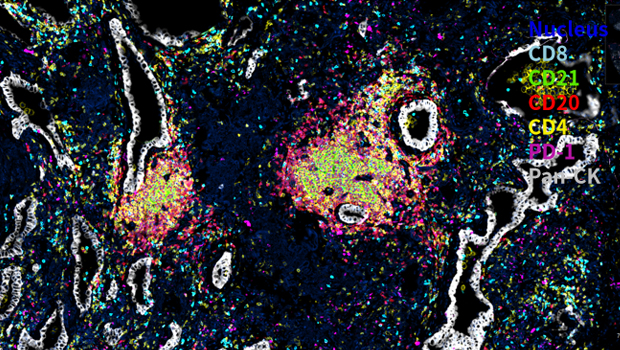

服务案例

Nucleus,CD8, CD21, CD20, CD4, PD-1,Pan-CK

通过识别组织图像中标志物的染色信息,自动调节荧光强度并识别出图像中 TLS 结构进行标注,进一步定量分析可得到图像中每个 TLS 独立的定量数据,同时可进一步对三级淋巴结构的内部进行空间分析。